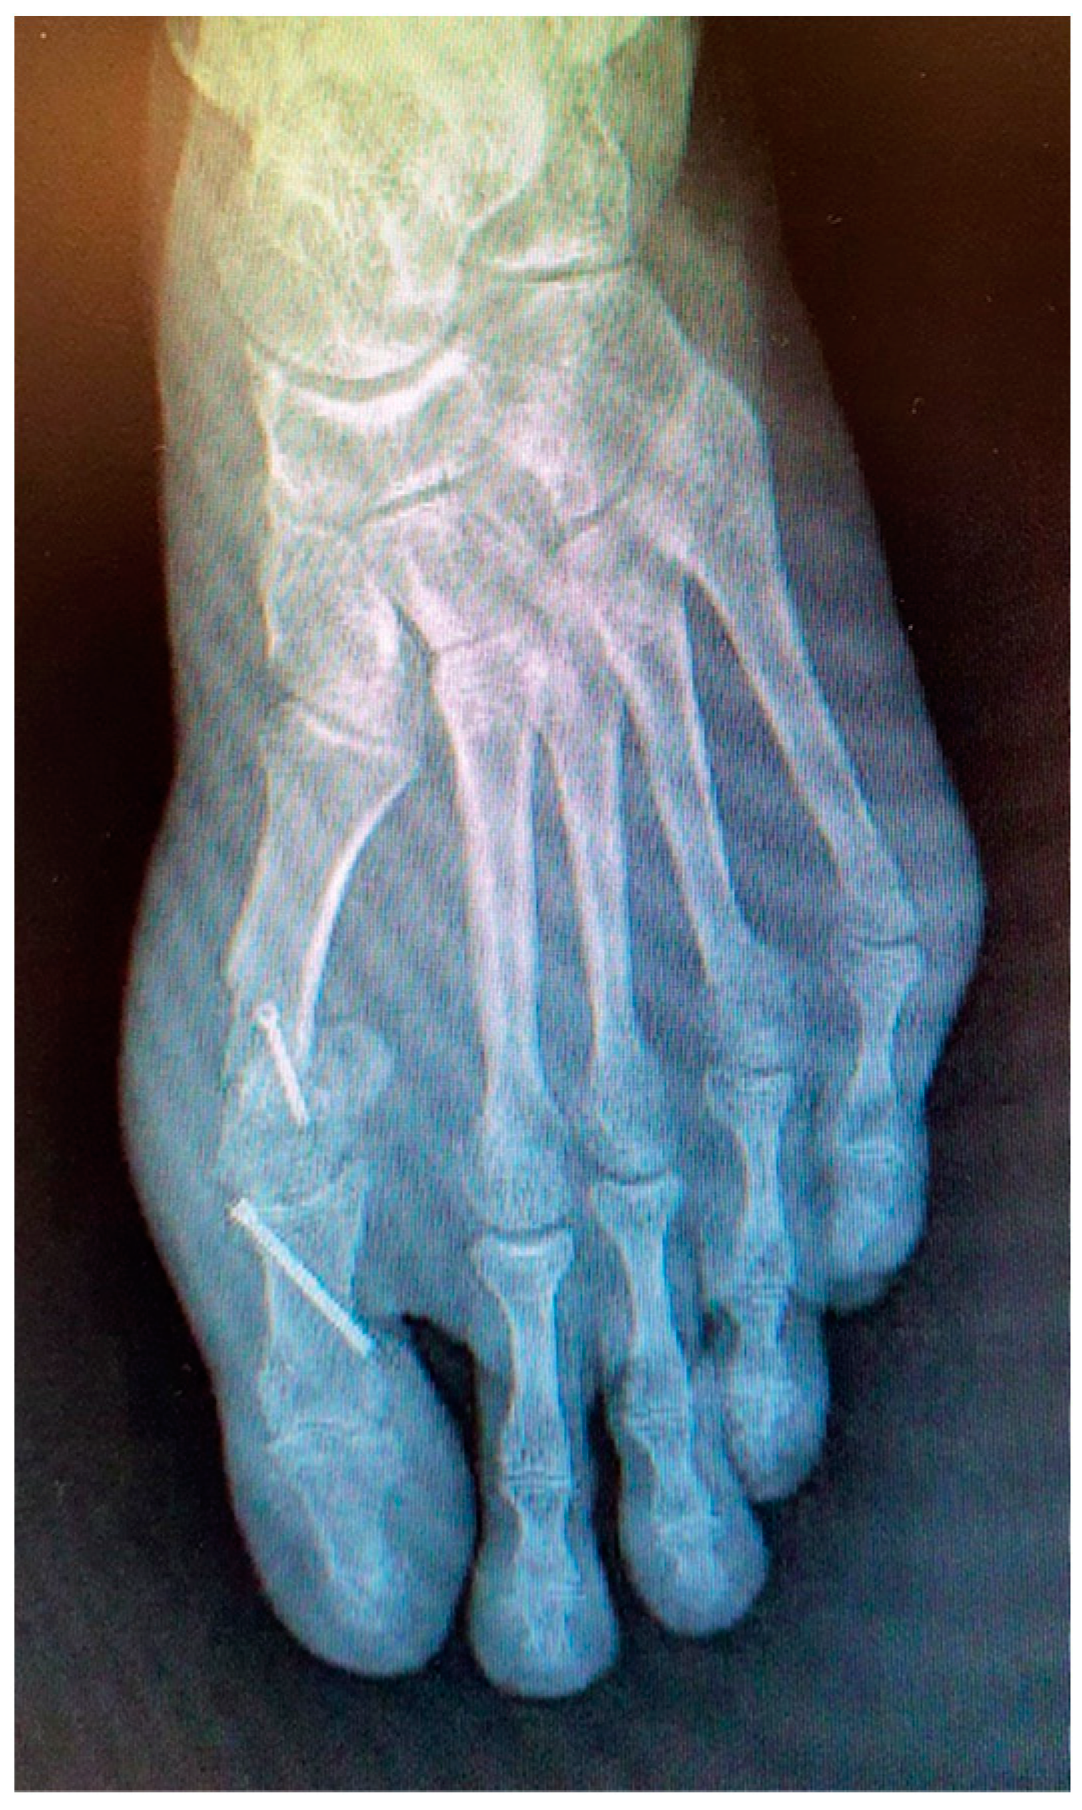

In May 2021, he underwent an operation to correct the hallux valgus deformity using chevron capital osteotomy and a proximal Akin procedure (Figure 1). The patient reported that a year later he had to be operated on again due to pain at the level of the first MPJ to remove the osteosynthesis material. The second surgery was performed outpatiently with epidural anaesthesia through a medial incision at the MPJ level (Figure 2).

Figure 1.

Postoperative radiological aspect of foot after the first procedure.